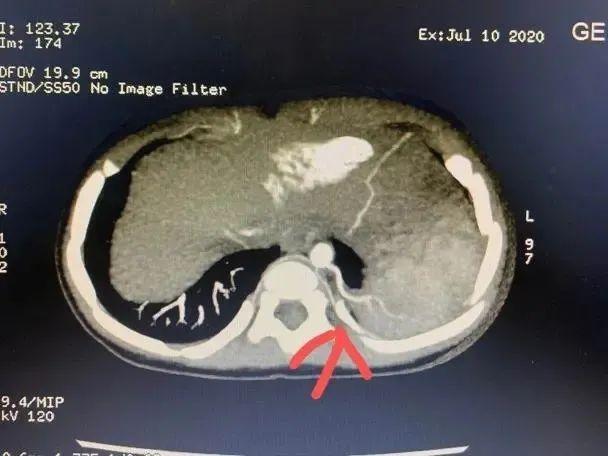

一个咳嗽这么难治愈吗?经过福建省福州儿童医院肺部CT检查,真相是小明的身体里“多了个肺”!!

医学上称为“肺隔离症”。

肺隔离症是一种先天性肺畸形,临床少见,其发病率约占先天性肺畸形的0.15% ~6.45%,一般无明显临床症状,多在合并肺内感染时与正常肺组织相通出现咳嗽、咳痰、咯血等症状,且反复发作,临床易误诊。

●其实质是由异常血管供血的肺囊肿症

●常与正常肺分开存在,有单独体循环血液供应

●增强CT结合三维血管重建发现异常供血可以确诊